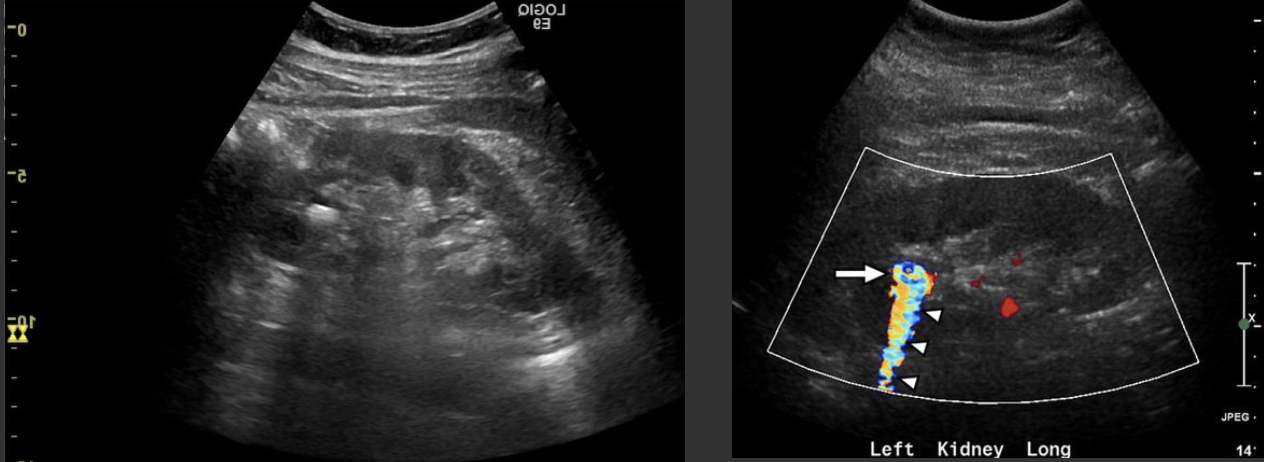

Renal Artery Stenosis → narrowing of renal artery

clinical hx: older adults, smoking, DM

s/sx: HTN that doesn’t respond to normal medical treatment

2D US: usually unilateral, compare affected kidney to unaffected, kidney is significantly smaller than contralateral kidney

color doppler: increased velocity in artery

DDX: atherosclerosis renal artery aneurysm